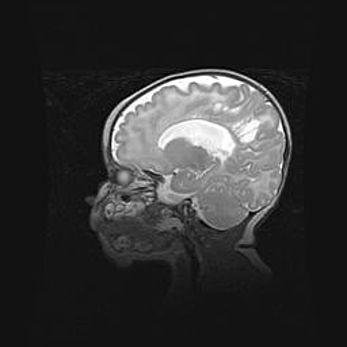

Ниже представлена  галерея МРТ снимков, полученных с применением LMT неонатальных матричных РЧ катушек. Также каждая группа МРТ снимков сопровождается информацией о пациенте (диагноз, возраст, вес, пол, срок гестации) и краткой сопроводительной расшифровкой диагноза.

Аномалия Денди-Уокера. Признаки гипоплазии мозолистого тела.

Возраст: 5 месяцев 3 дня

Вес: 5550 г

Пол: мужской

Окружность головы: 39 см

Срок гестации: 40 недель

Аномалия Денди-Уокера – это порок развития головного мозга, для которого характерна триада симптомов: гипотрофия или аплазия червя мозжечка и/или полушарий мозжечка, расширение четвёртого желудочка с формированием ликворной кисты задней черепной ямки, гипертензионная гидроцефалия различной степени.

Гипоплазия мозолистого тела относится к дефектам внутриутробного этапа развития мозговой ткани, возникающим в процессе закладки структур головного мозга, что происходит на начальных этапах развития эмбриона.